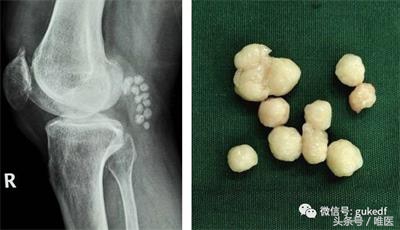

8. 对于关节内软骨剥脱形成游离体,以及半月板撕裂产生卡压、交锁症状的患者可以考虑膝关节镜下清理游离体(图4)和增生的滑膜组织,或镜下微创缝合损伤撕裂的半月板(图5)。前(后)交叉韧带断裂的可行关节镜下的韧带重建手术(图6)。

图4. 膝关节镜清理游离体